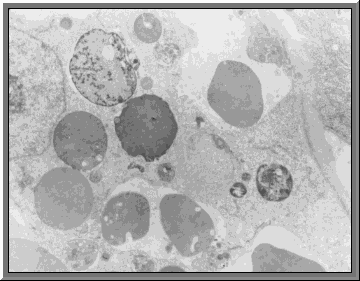

The syncytiotrophoblast

The outer layer of the trophoblast the syncytiotrophoblast evolves from the cytotrophoblast The cells of the cytotrophoblast duplicate their DNA, followed by an increase of cytoplasm. There is, however, no cell division. This results in the formation of a syncytium.

The cytotrophoblast which implants actively into the endometrium undergoes a considerable increase in thickness.